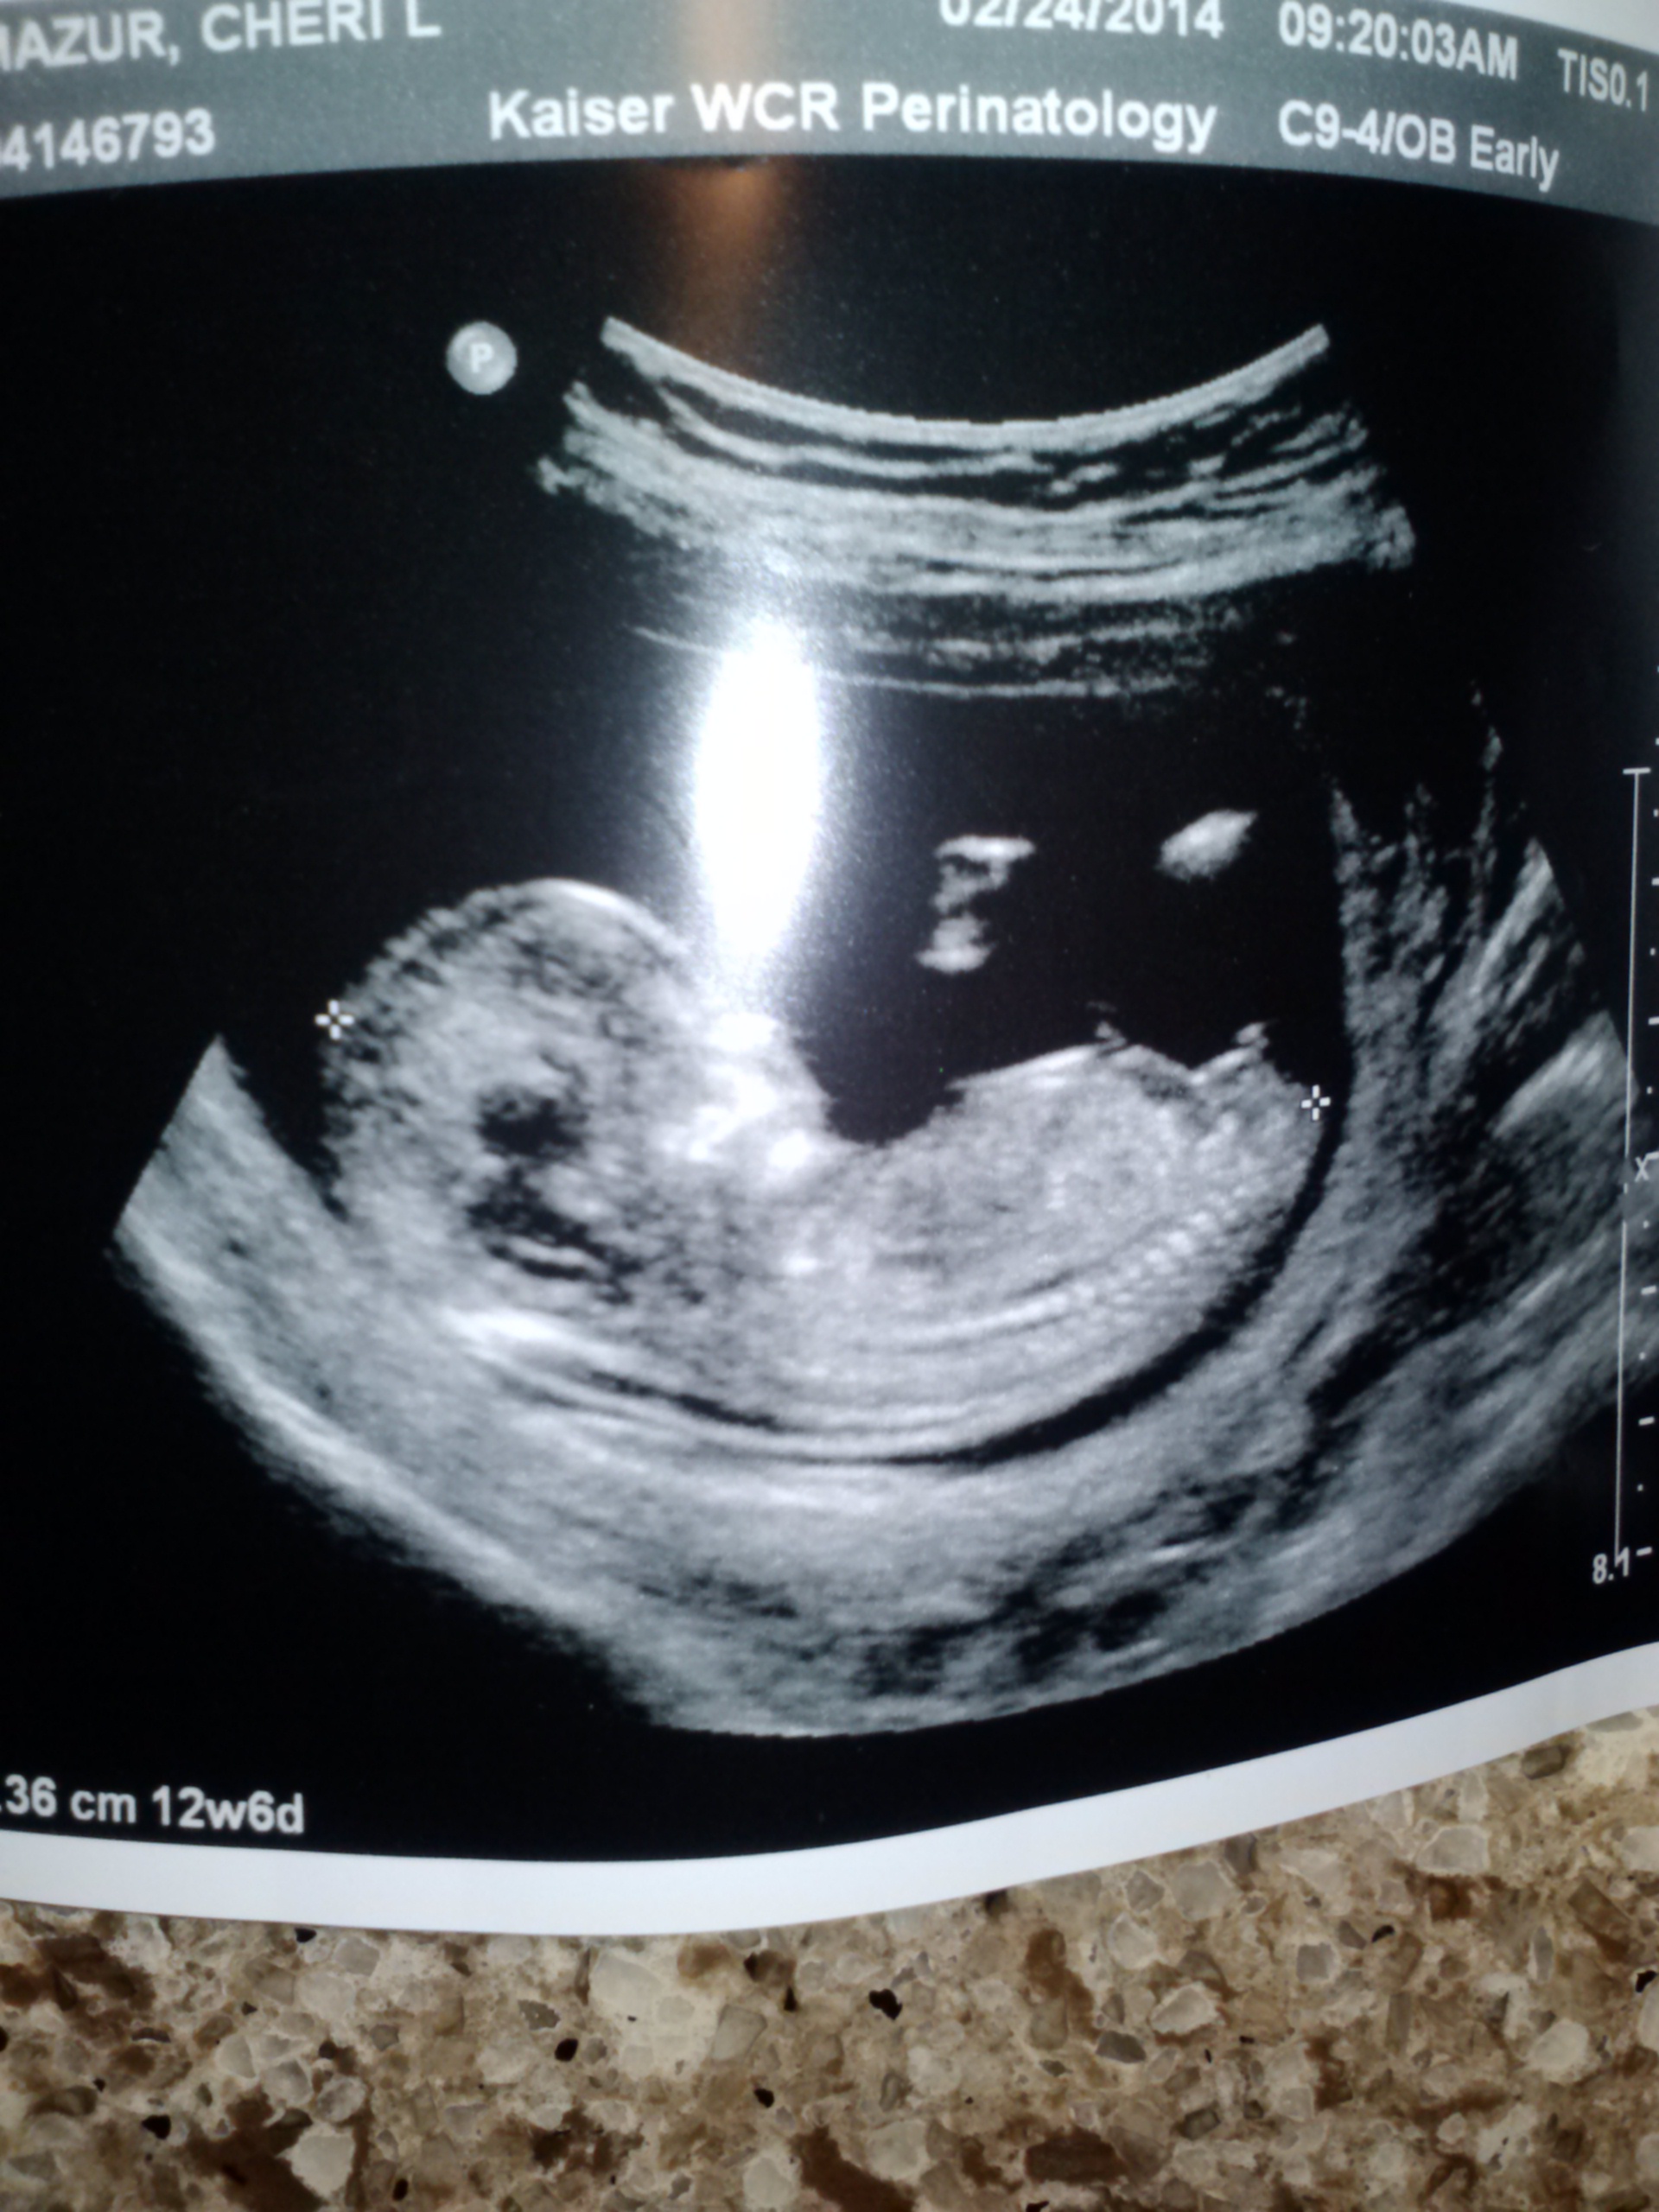

Attachment 17967

Looks like a boy!

What about when you look at the potty shot....it was very early so maybe not reliable.....but in a close up i swear i see two round testicles or??? But i dont really see a weiner in between....the nub is early too so i am driving myself crazy with this! I cannot tell you how bad i want a boy......t

Nub looks very boyish. Goodluck

I would say boy! Good luck.

Looks like a very boyish nub to me!

Your second shot is a very clear boy nub!

Looks like a boy nub to me!

The nub shot is very boyish.

Clear boy nub in 2nd shot

boy :)